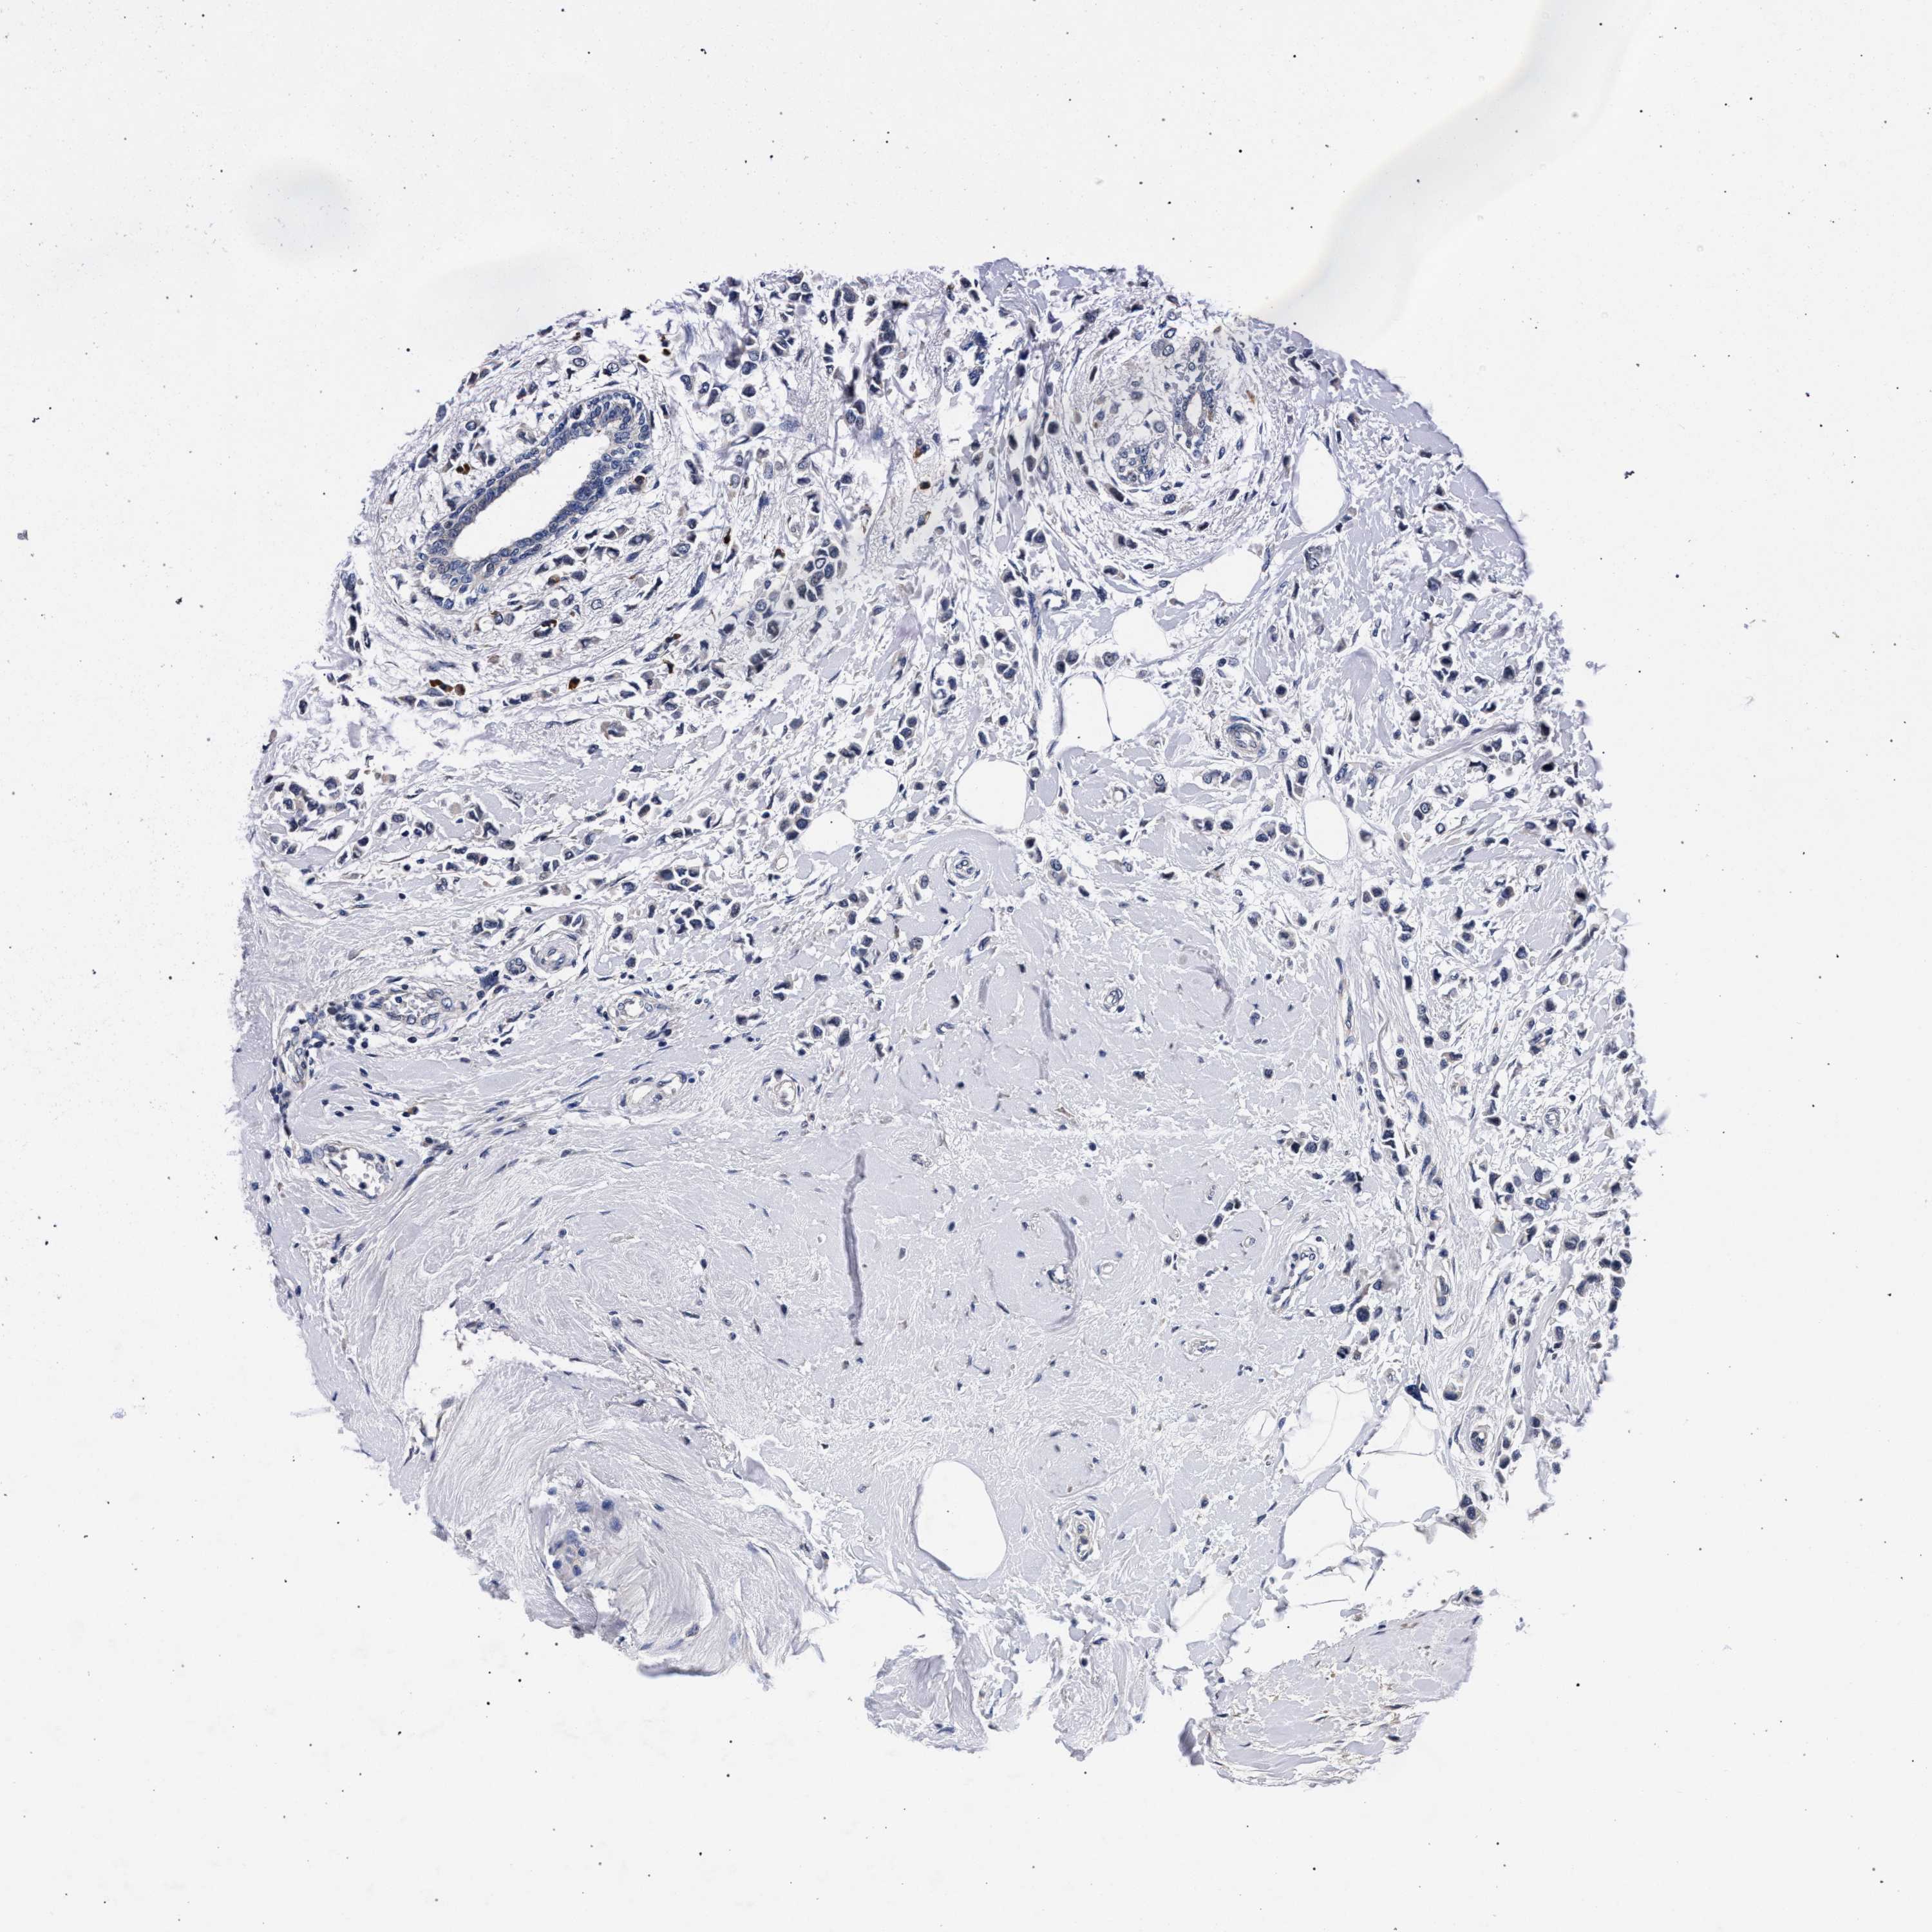

CANCER BREAST CANCER Show tissue menu

BRCA TCGA BRCA VALIDATION PROTEIN EXPRESSION

ANTIBODIES

AND

VALIDATION